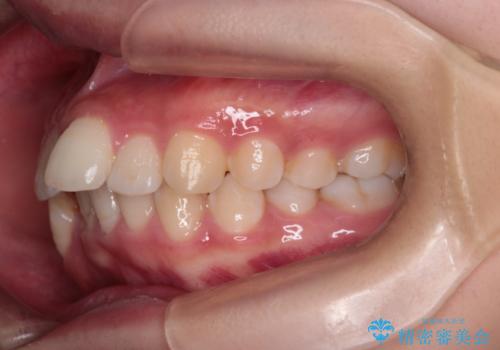

今回の治療では、重度の叢生を改善するため、まず計画通り上下左右4本の小臼歯を抜歯し、歯を並べるための十分なスペースを確保しました。装置には透明で取り外し可能なインビザラインを使用。抜歯によってできたスペースを最大限に活用し、マウスピースを定期的に交換しながら、デコボコを解消しつつ、前歯を効果的に後退させました。

治療の結果、長年の悩みであった重度の歯のがたつきが解消され、口元の突出感も改善。機能的にも安定し、審美的にも美しい、理想的な歯並びを獲得していただけました。